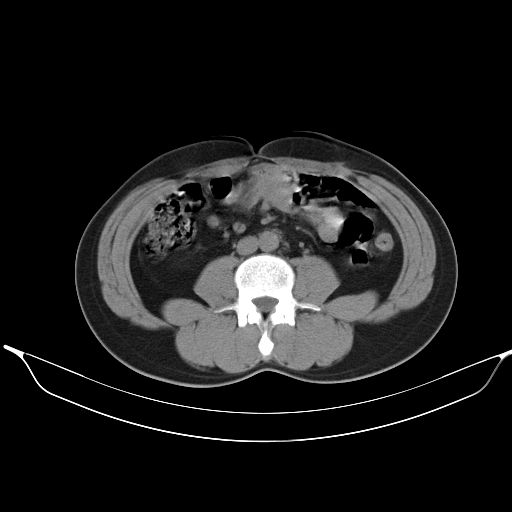

2、轻度脂肪肝。

1、均为转移,原发灶不在肺内。2、肺癌肺转移。